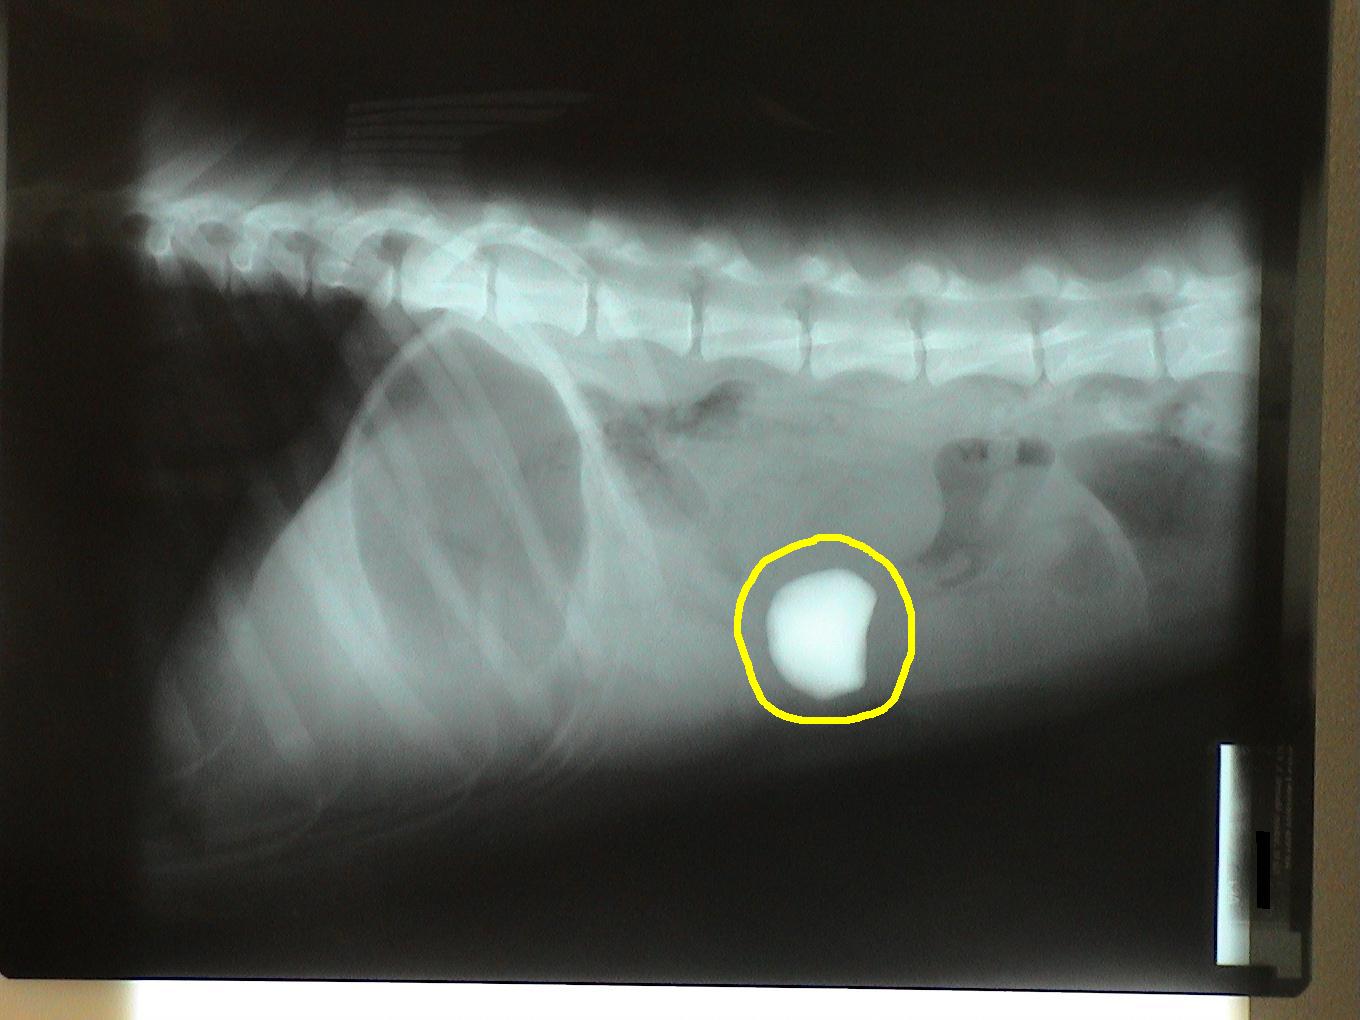

Let's identify the foreign bodies in each of these x-rays.

This is a trick question. This is a pregnant dog. Each skull is circled in blue.